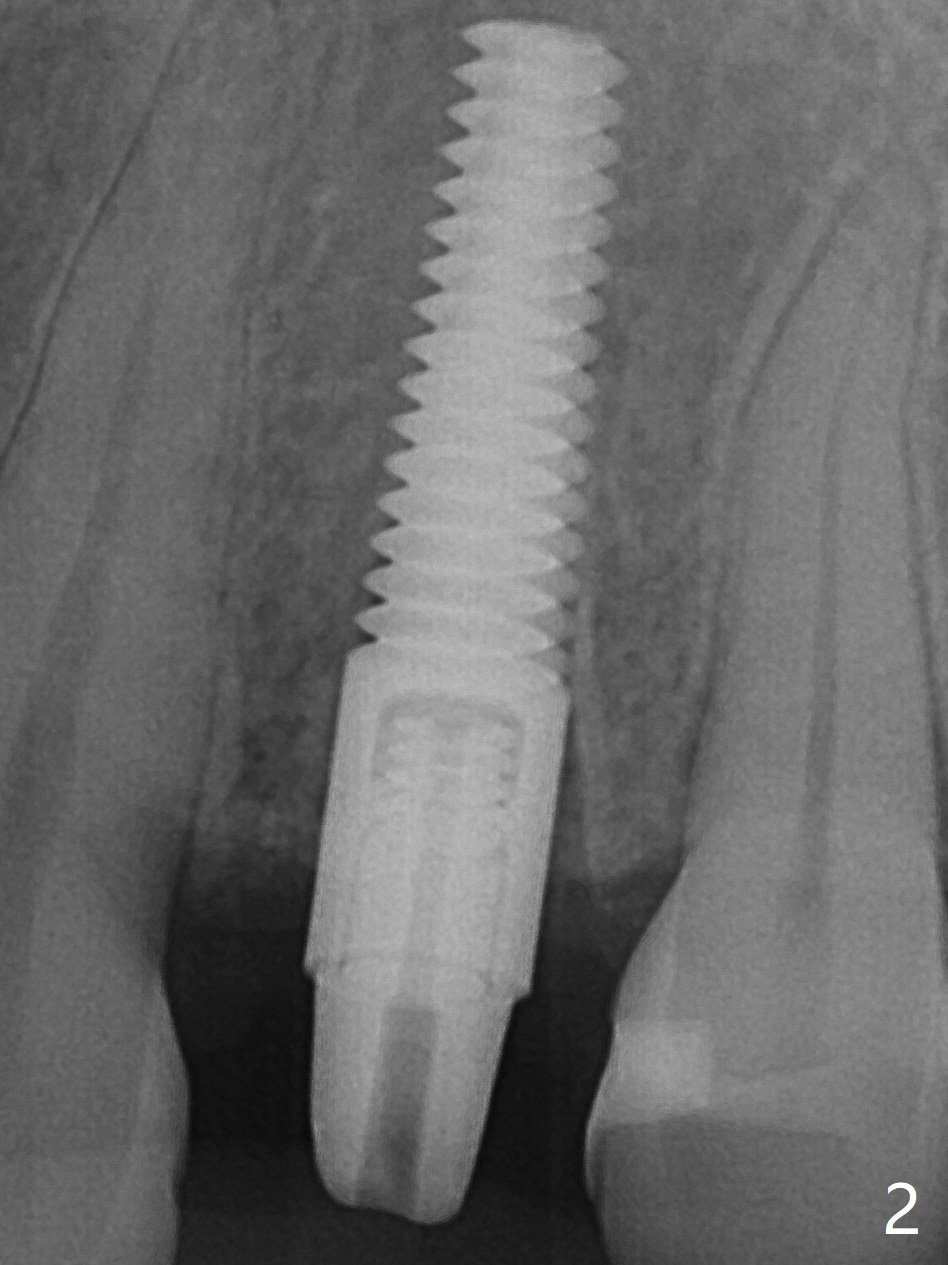

Since there is no buccal plate atrophy at 4, or 8, socket shield is not attempted at #31. Extraction turns out to be difficult because of tooth fracture. The buccal and palatal flaps have to be elevated minimally for tooth sectioning and purchase point formation. More surprising, a 4.5 mm implant appears to be too wide for the space; a 4x17 mm implant achieves insertion torque >60 Ncm (Fig.1,2). In fact Vanilla graft is placed before and after implantation. The advantage of bone graft before implant is that the graft is able to be placed as apical as possible to repair the apical defect if it is present. The disadvantage is hemorrhage. After placement of a 3.5x5 mm abutment, an immediate provisional is fabricated (Fig.3 P), which seems to be able to hold the separated buccal papillae in place. The latter heal around the immediate provisional 9 days postop (Fig.4). Because of the seal, the bone graft remains in place 1 month postop (Fig.5). There is no bone loss 5.5 months postop (Fig.6,7) or 6.5 months postop (immediately post cementation, Fig.8).